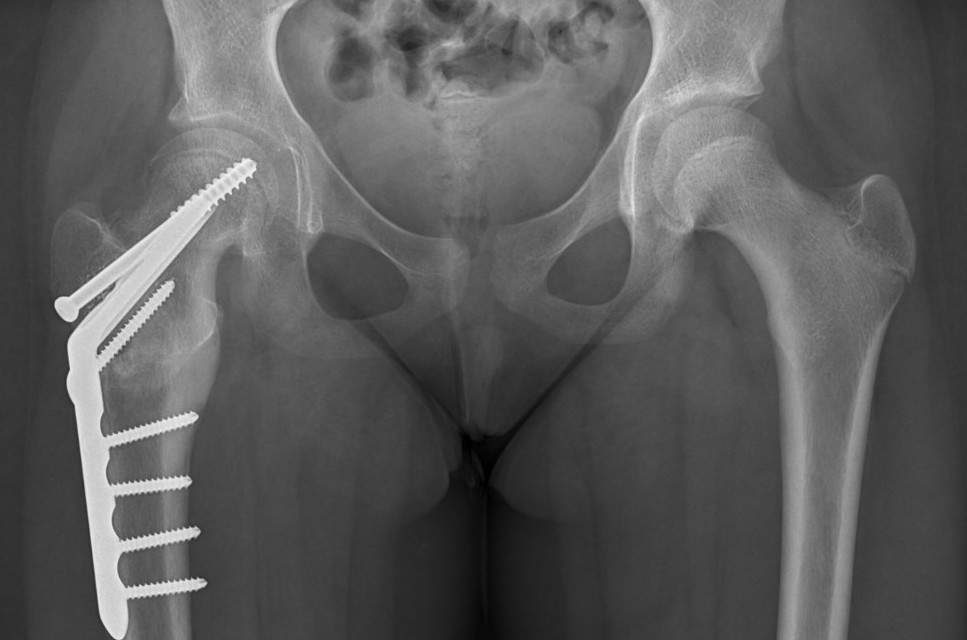

Intertrochanteric / Southwick

Technique

Removal anterolateral bone wedge below lesser trochanter

Valgising / flexion / internal rotation